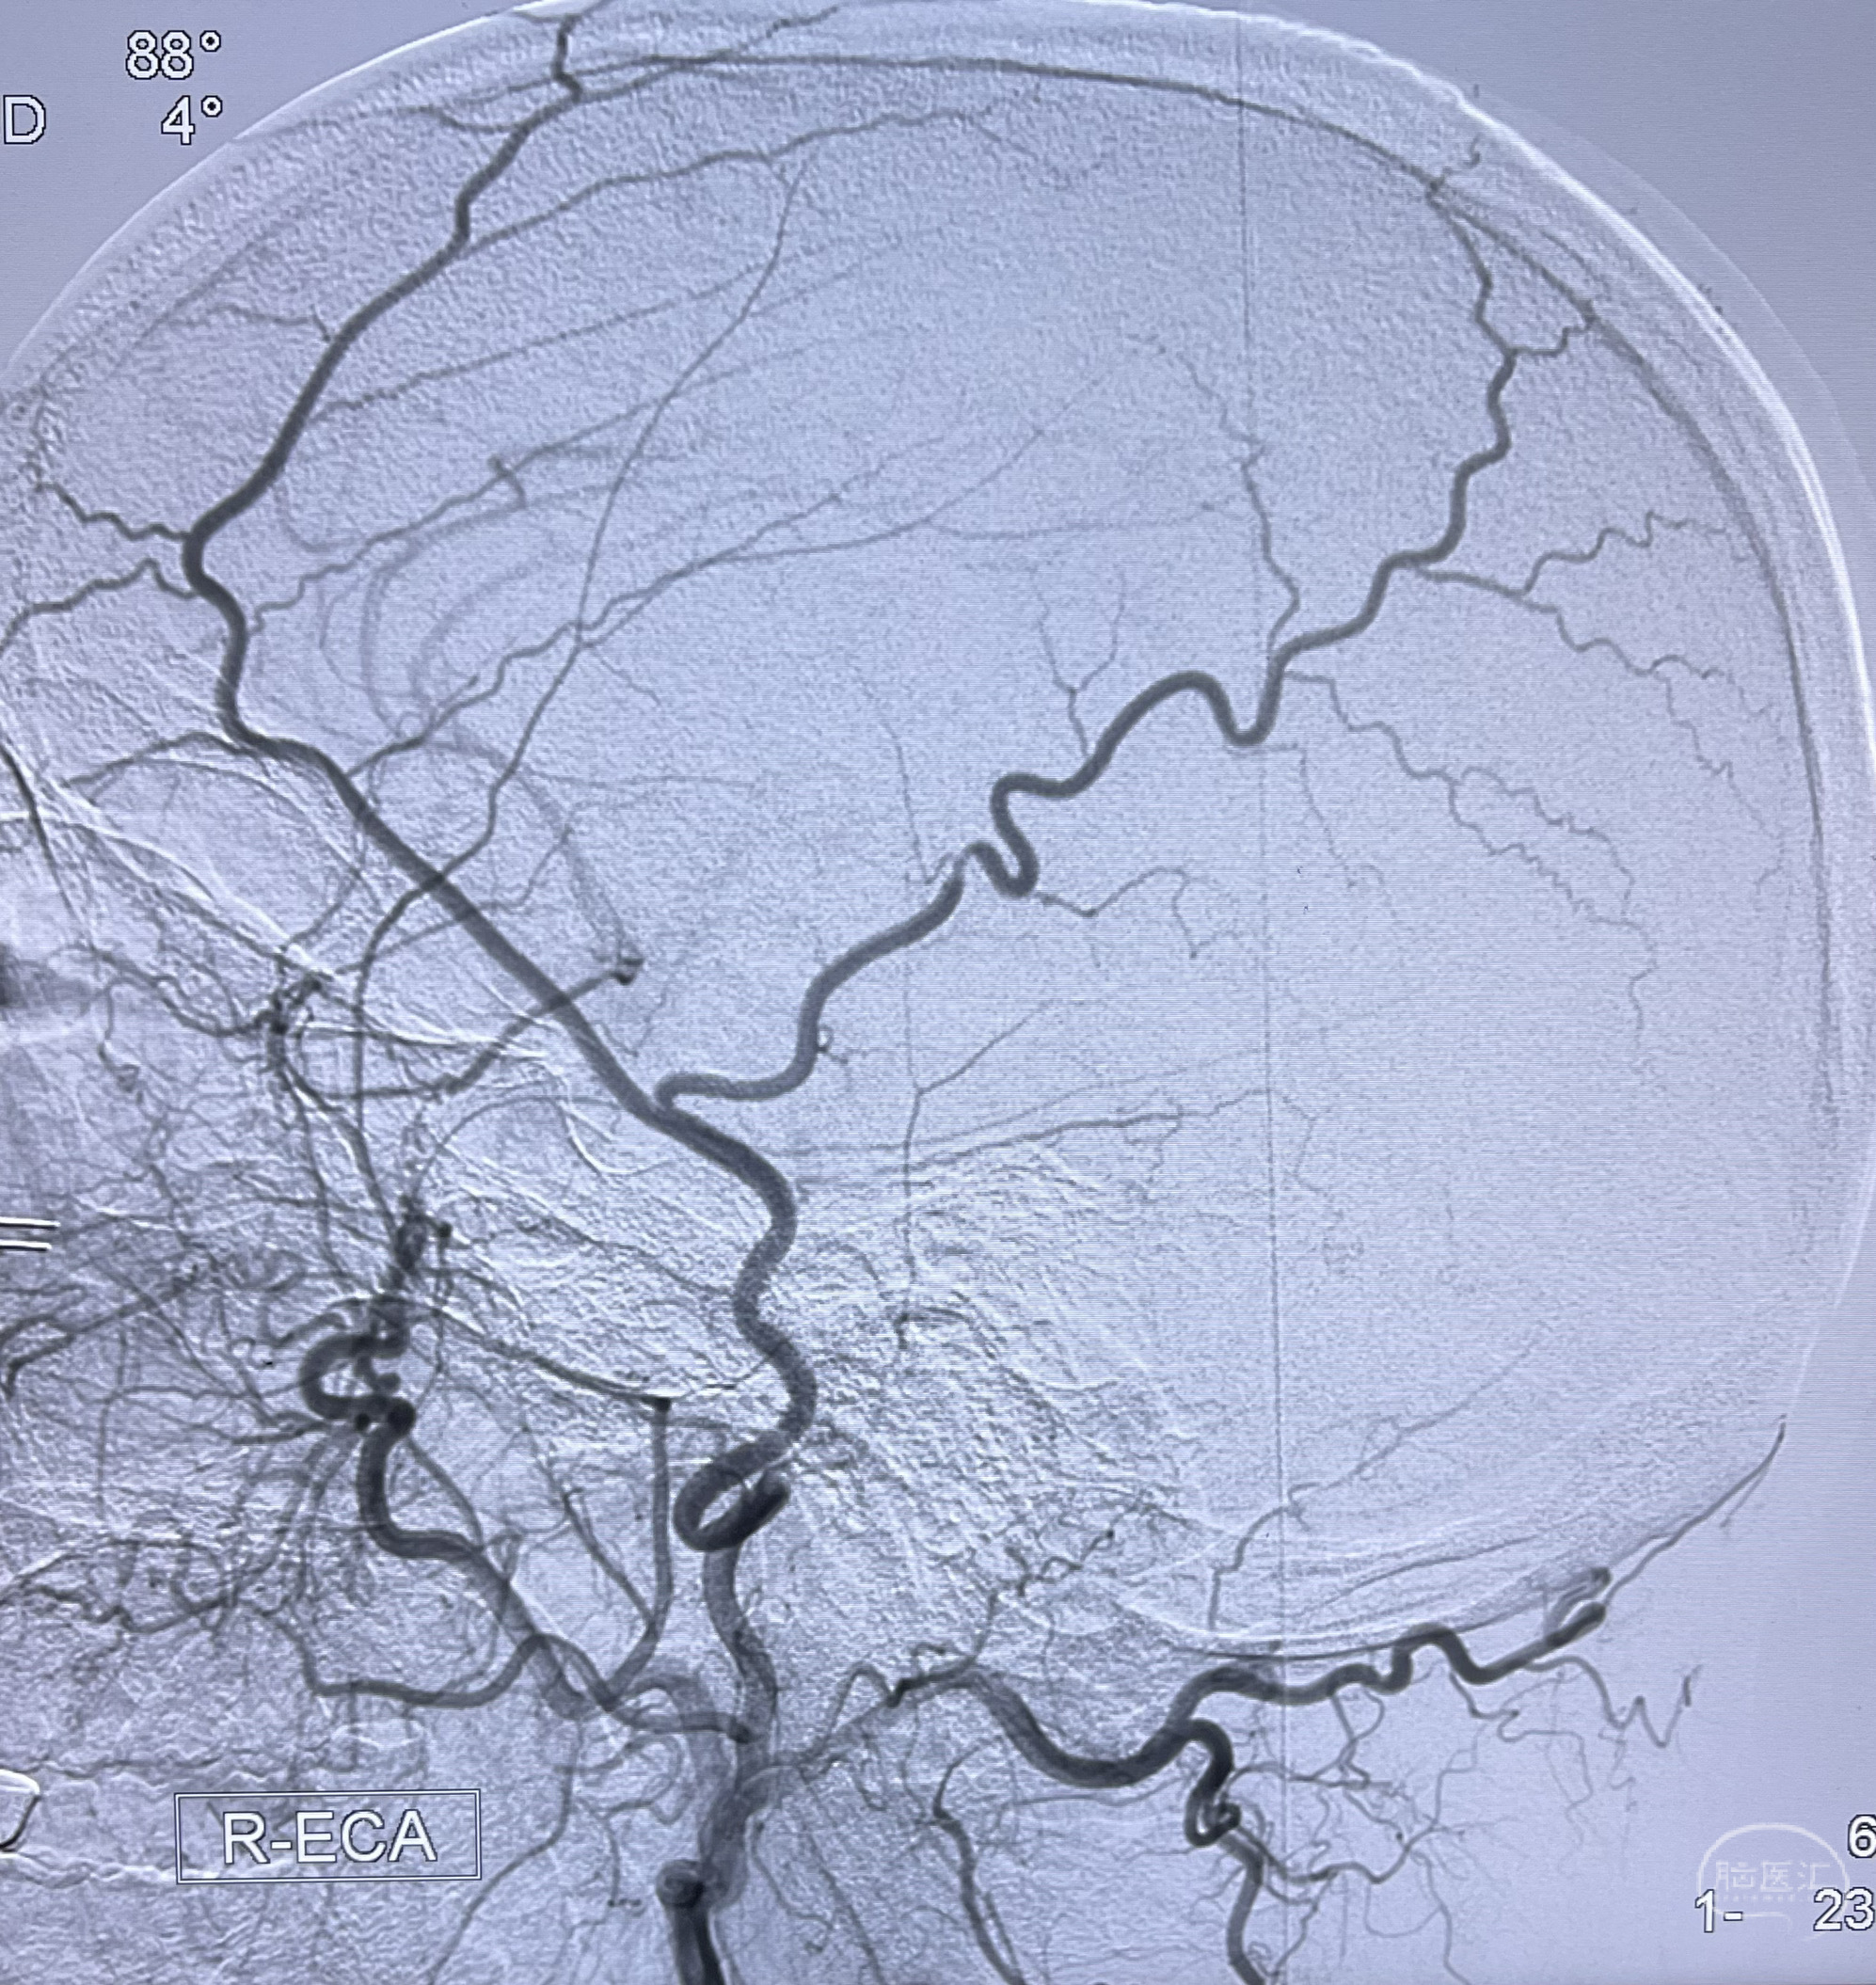

4.右侧颈外动脉可见经由右侧脑膜中动脉吻合显影右侧眼动脉及颈内动脉

6.左侧颈外动脉可见吻合显影至左侧椎动脉并逆行供血至左侧腋动脉

左侧颈外动脉经脑膜支吻合至左侧椎动脉—左侧锁骨下动脉—左侧上肢

左侧肾动脉重度狭窄